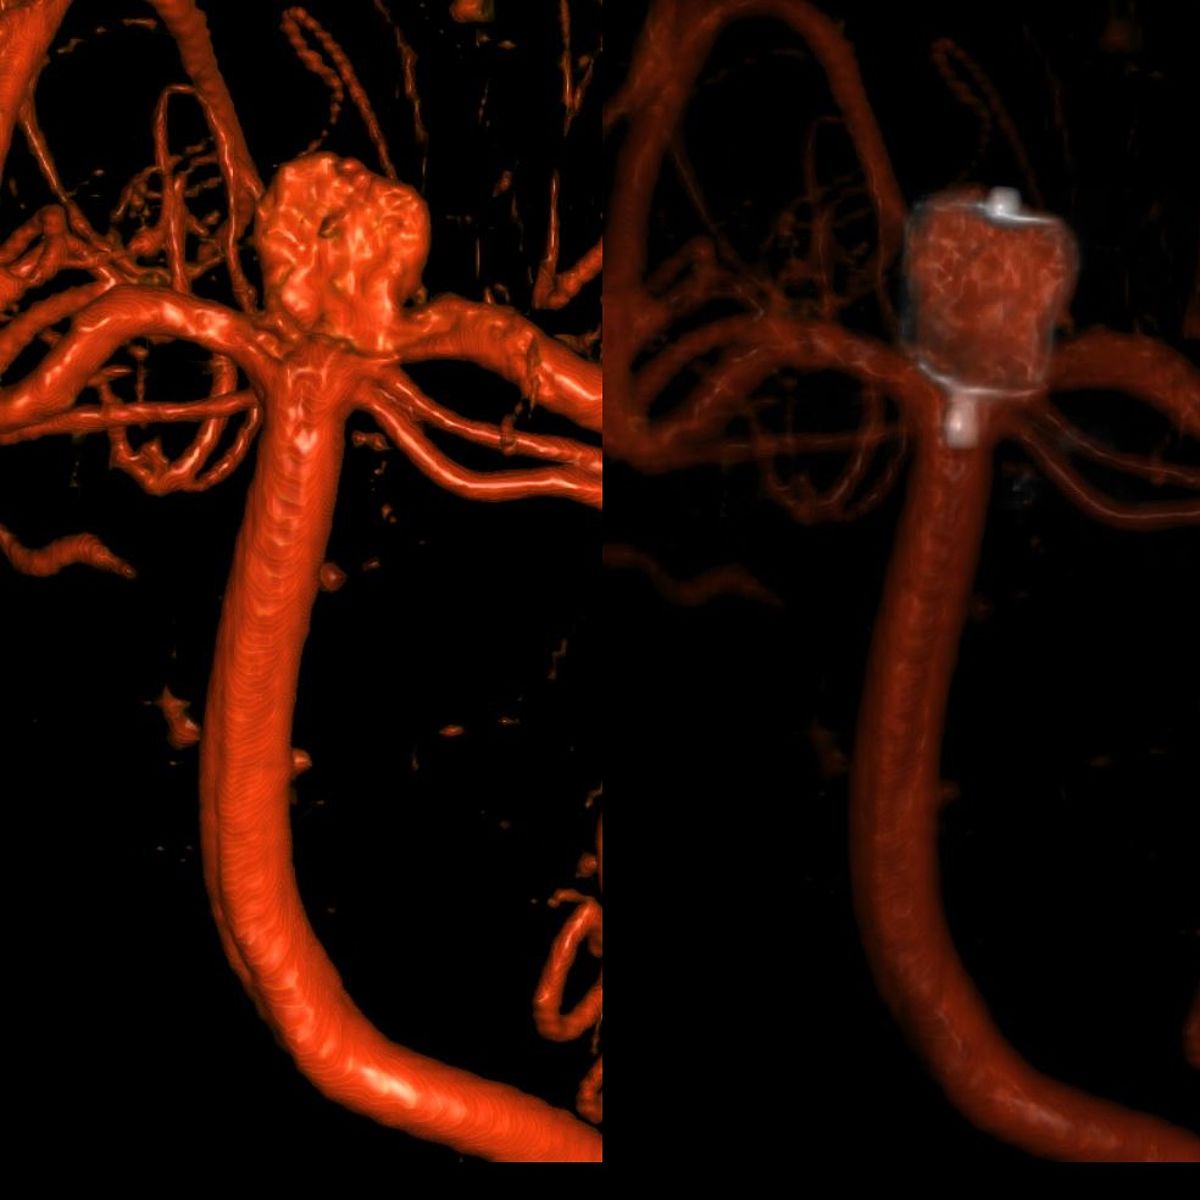

In Augsburg werden im Jahr etwa 80 solcher akuter Subarachnoidealblutungen behandelt. Dabei ist neben der Behandlung der Blutungsfolgen vor allem die Ausschaltung des ursächlichen Aneurysmas dringlich, was meist interventionell durch die Neuroradiologie erfolgt.

Insgesamt behandeln wir etwa 180 Aneurysmen im Jahr.